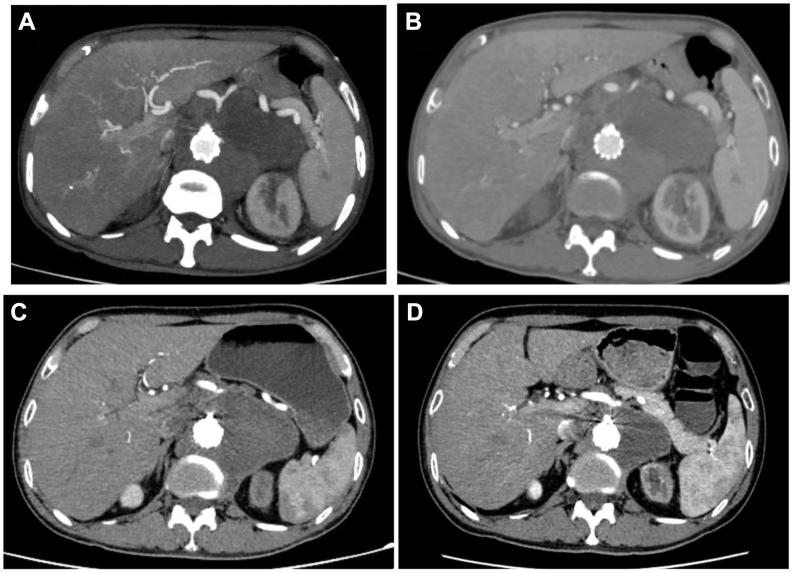

Tuberculous abdominal aortic pseudoaneurysm is a severe vascular disease that is exceptionally rare and carries a high risk of rupture. This article reports the rupture of a pseudoaneurysm in a 60-year-old male patient during anti-tuberculosis treatment. The patient's general condition was poor, making him unable to tolerate open surgical treatment. Therefore, endovascular aortic aneurysm repair was performed. The rupture site of the patient's aneurysm was located next to the visceral artery (between the superior mesenteric and renal arteries). During the surgery, we used three-dimensional printing technology to perform fenestrated endovascular repair. The surgery successfully excluded the aneurysm while ensuring blood supply to the visceral arteries. After discharge, the patient received regular anti-tuberculosis treatment. Postoperative follow-up revealed no graft-related complications, and the visceral artery remained unobstructed.

摘要

结核性腹主动脉假性动脉瘤是一种极为罕见的严重血管疾病,破裂风险很高。本文报道了一名60岁男性患者在抗结核治疗期间假性动脉瘤破裂的病例。患者一般状况较差,无法耐受开放手术治疗。因此,实施了血管腔内主动脉瘤修复术。患者动脉瘤的破裂部位位于内脏动脉旁(肠系膜上动脉和肾动脉之间)。手术中,我们使用三维打印技术进行开窗血管腔内修复。手术成功排除了动脉瘤,同时确保了内脏动脉的血供。出院后,患者接受了规律的抗结核治疗。术后随访未发现与移植物相关的并发症,内脏动脉保持通畅。